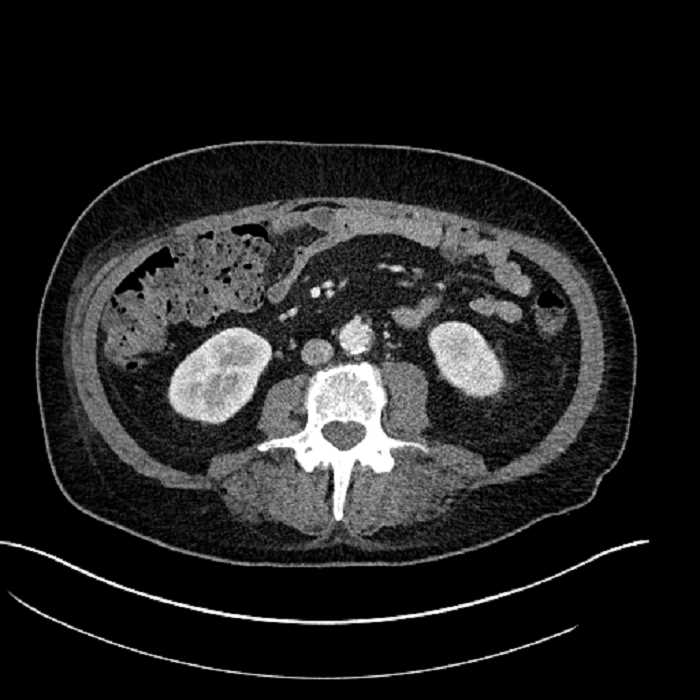

Age: 63

Sex: Male

Indication: Abdominal pain

• Large fluid density structure in hepatic segments 7 and 8 measuring 10 x 7 x 7 cm with internal septation and circumferential ill-defined low density compatible with edema

• Peripherally enhancing subcapsular collections along the anterior margin of the left hepatic lobe measuring 3 x 1 cm and 2 x 1 cm

• Clearly marginated fluid density structure in segment 7 and several other scattered tiny hypodensities, which likely represent cysts

Acute sigmoid diverticulitis complicated by a small contained perforation and a large abscess in the right hepatic lobe. Additional small subcapsular abscesses along the anterior margin of the left hepatic lobe.

• The classic CT imaging appearance is a double target sign with internal low density surrounded by an internal enhancing rim (capsule) and a low density external rim (edema)

Hepatic abscess showing the double target sign with low density internally surrounded by a thin inner enhancing rim (red arrow) and ill-defined outer low density rim (yellow arrow). Blue arrow indicates an internal septation. Red arrows: additional smaller subcapsular abscesses. Red arrow: focal contained perforation associated with diverticulitis.